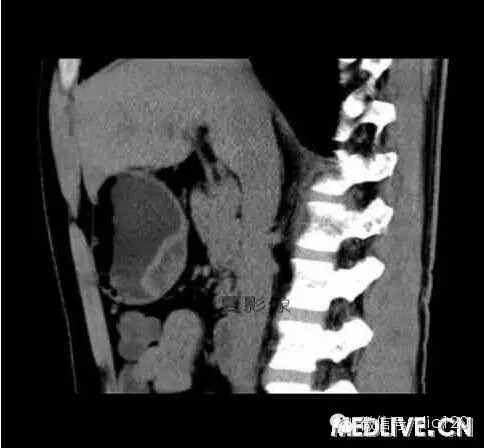

| 病史资料: | 男,36岁,间断性返酸嗳气3年,3个月前出现上腹疼痛,饥饿时加重。图1-3为CT平扫,图4-6分别为CT增强扫描的动脉期、门脉期和延迟期. |

| 影像表现及分析: | CT检查可见胃幽门前区胃小弯侧胃壁局限性增厚、隆起或伴凸向胃腔内的小结节灶,宽基地,境界光整,注射对比剂,增强扫描后,CT值可达50HU以上,与正常胰腺强化相仿。 |

| 疾病总结: | 胃迷走胰腺大多位在距幽门1-6cm的胃窦胃大弯侧,粘膜下层内,为1-3cm大小的病灶。 与胃壁以宽基底相,增强扫描病灶表面覆盖的黏膜明显强化且连续,病灶内无明显坏死,病变强化方式类似于正常胰腺组织;当病灶出现边缘脐凹征或中央导管征时,对EP的诊断具有一定的特异性。 |